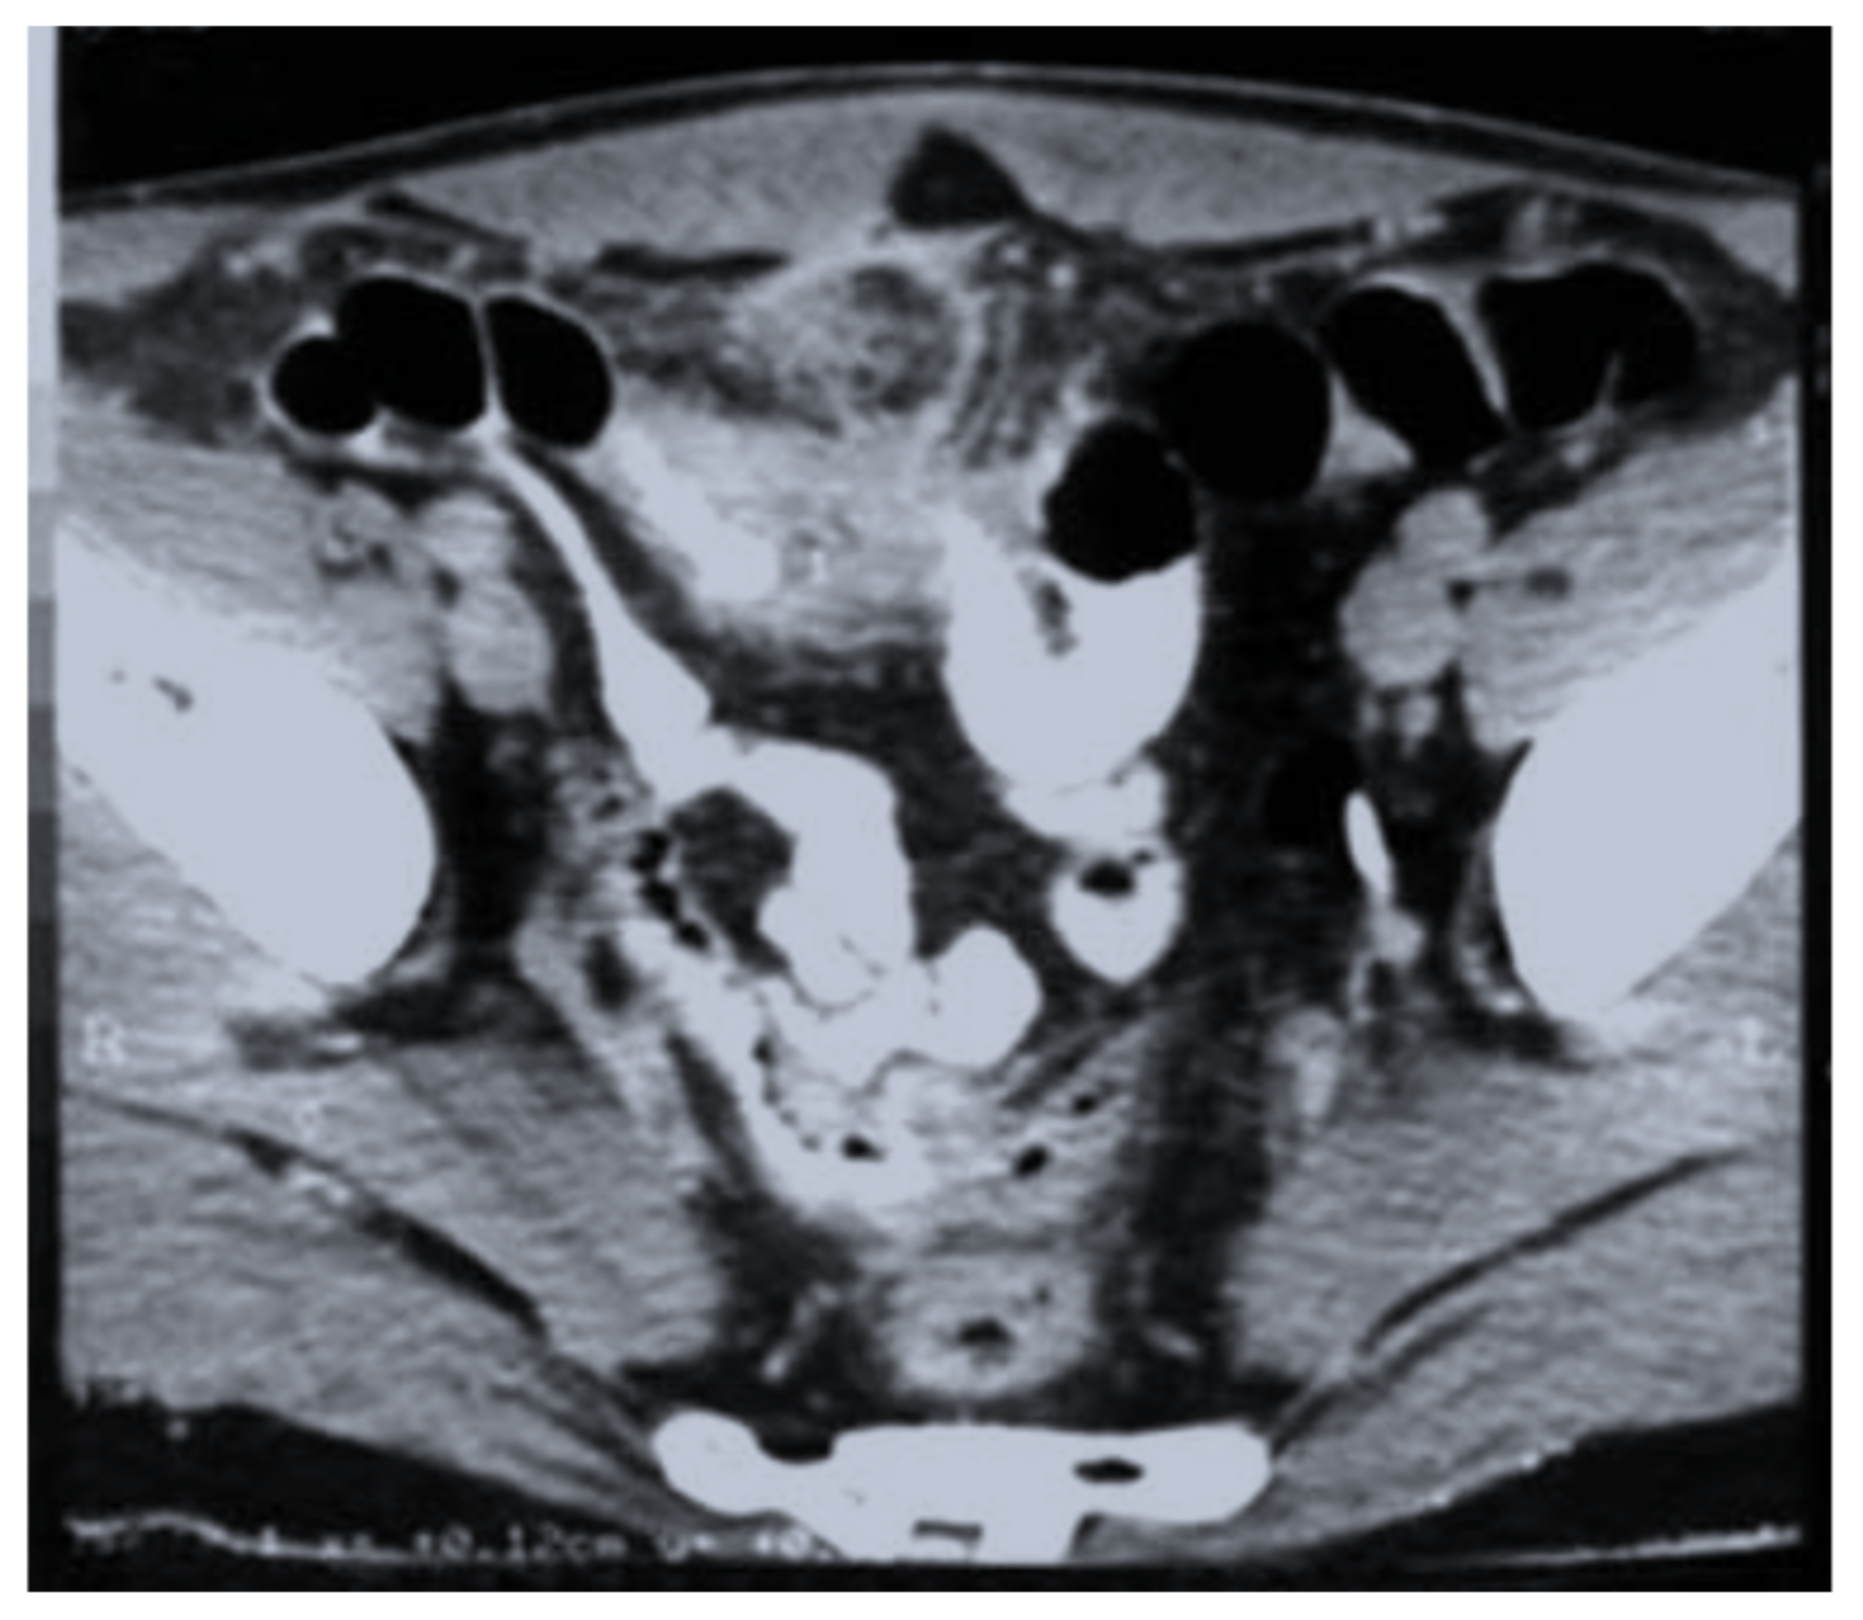

| Imaging (US, CT) characteristic | N (cases) (%) |

| Intraperitoneal collections | 11/28 (39.2%) |

| A heterogeneous mass involving the colon | 6/28 (21.4%) |

| Omental mass | 3/28 (10.7%) |

| Inflammatory mass involving the ovaries | 6/28 (21.4%) |

| Right liver abscesses | 2/28 (7.1%) |